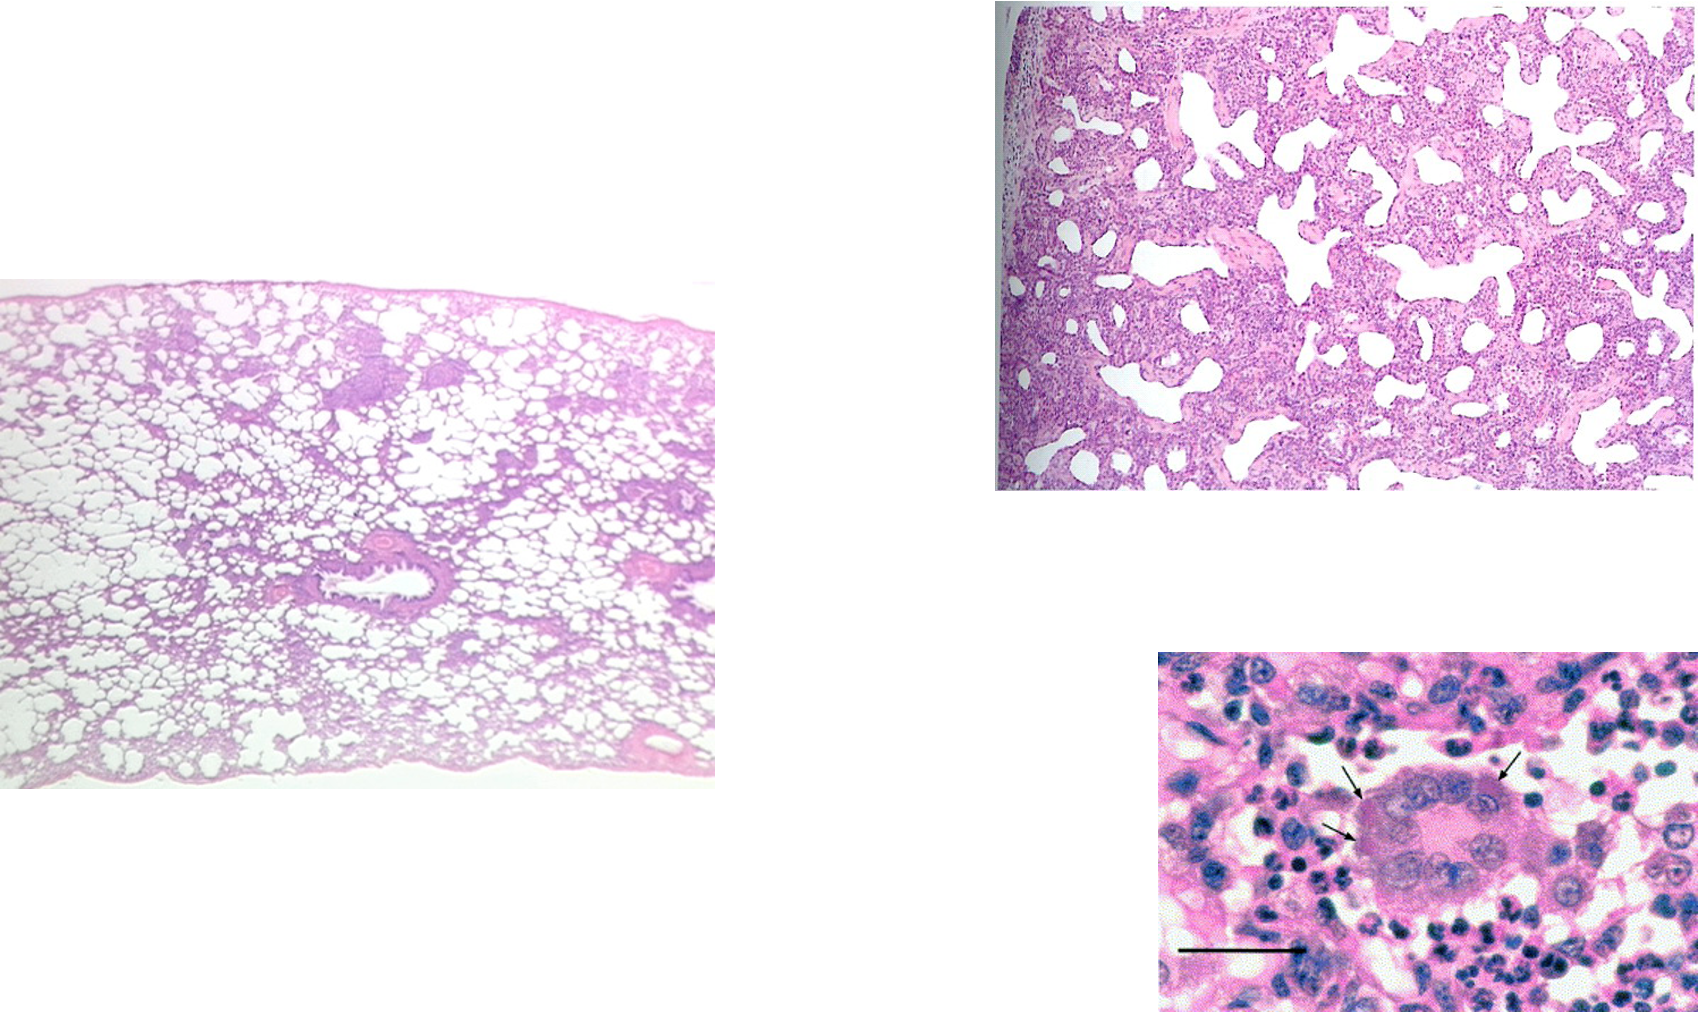

How does BRSV present histologically?

Thickened alveoli septae by lymphocytes and mononuclear cells

^^ normal on L, R = tissue between alveoli infected w/ RSV -> inflam cells, MNGCs -> difficult exchange of gas across thicker surface

formation of Giant cells in the epithelial lining and in the lumen of the bronchioles and alveoli causing obstruction of airways and impairs lung clearance mechanisms, predisposing to secondary bacterial bronchopneumonia.

MNGCs = chronic inflam

^^ alveolar wall thickening on L, normal on R

How does BRSV present grossly?

Characterised by bullae on surface